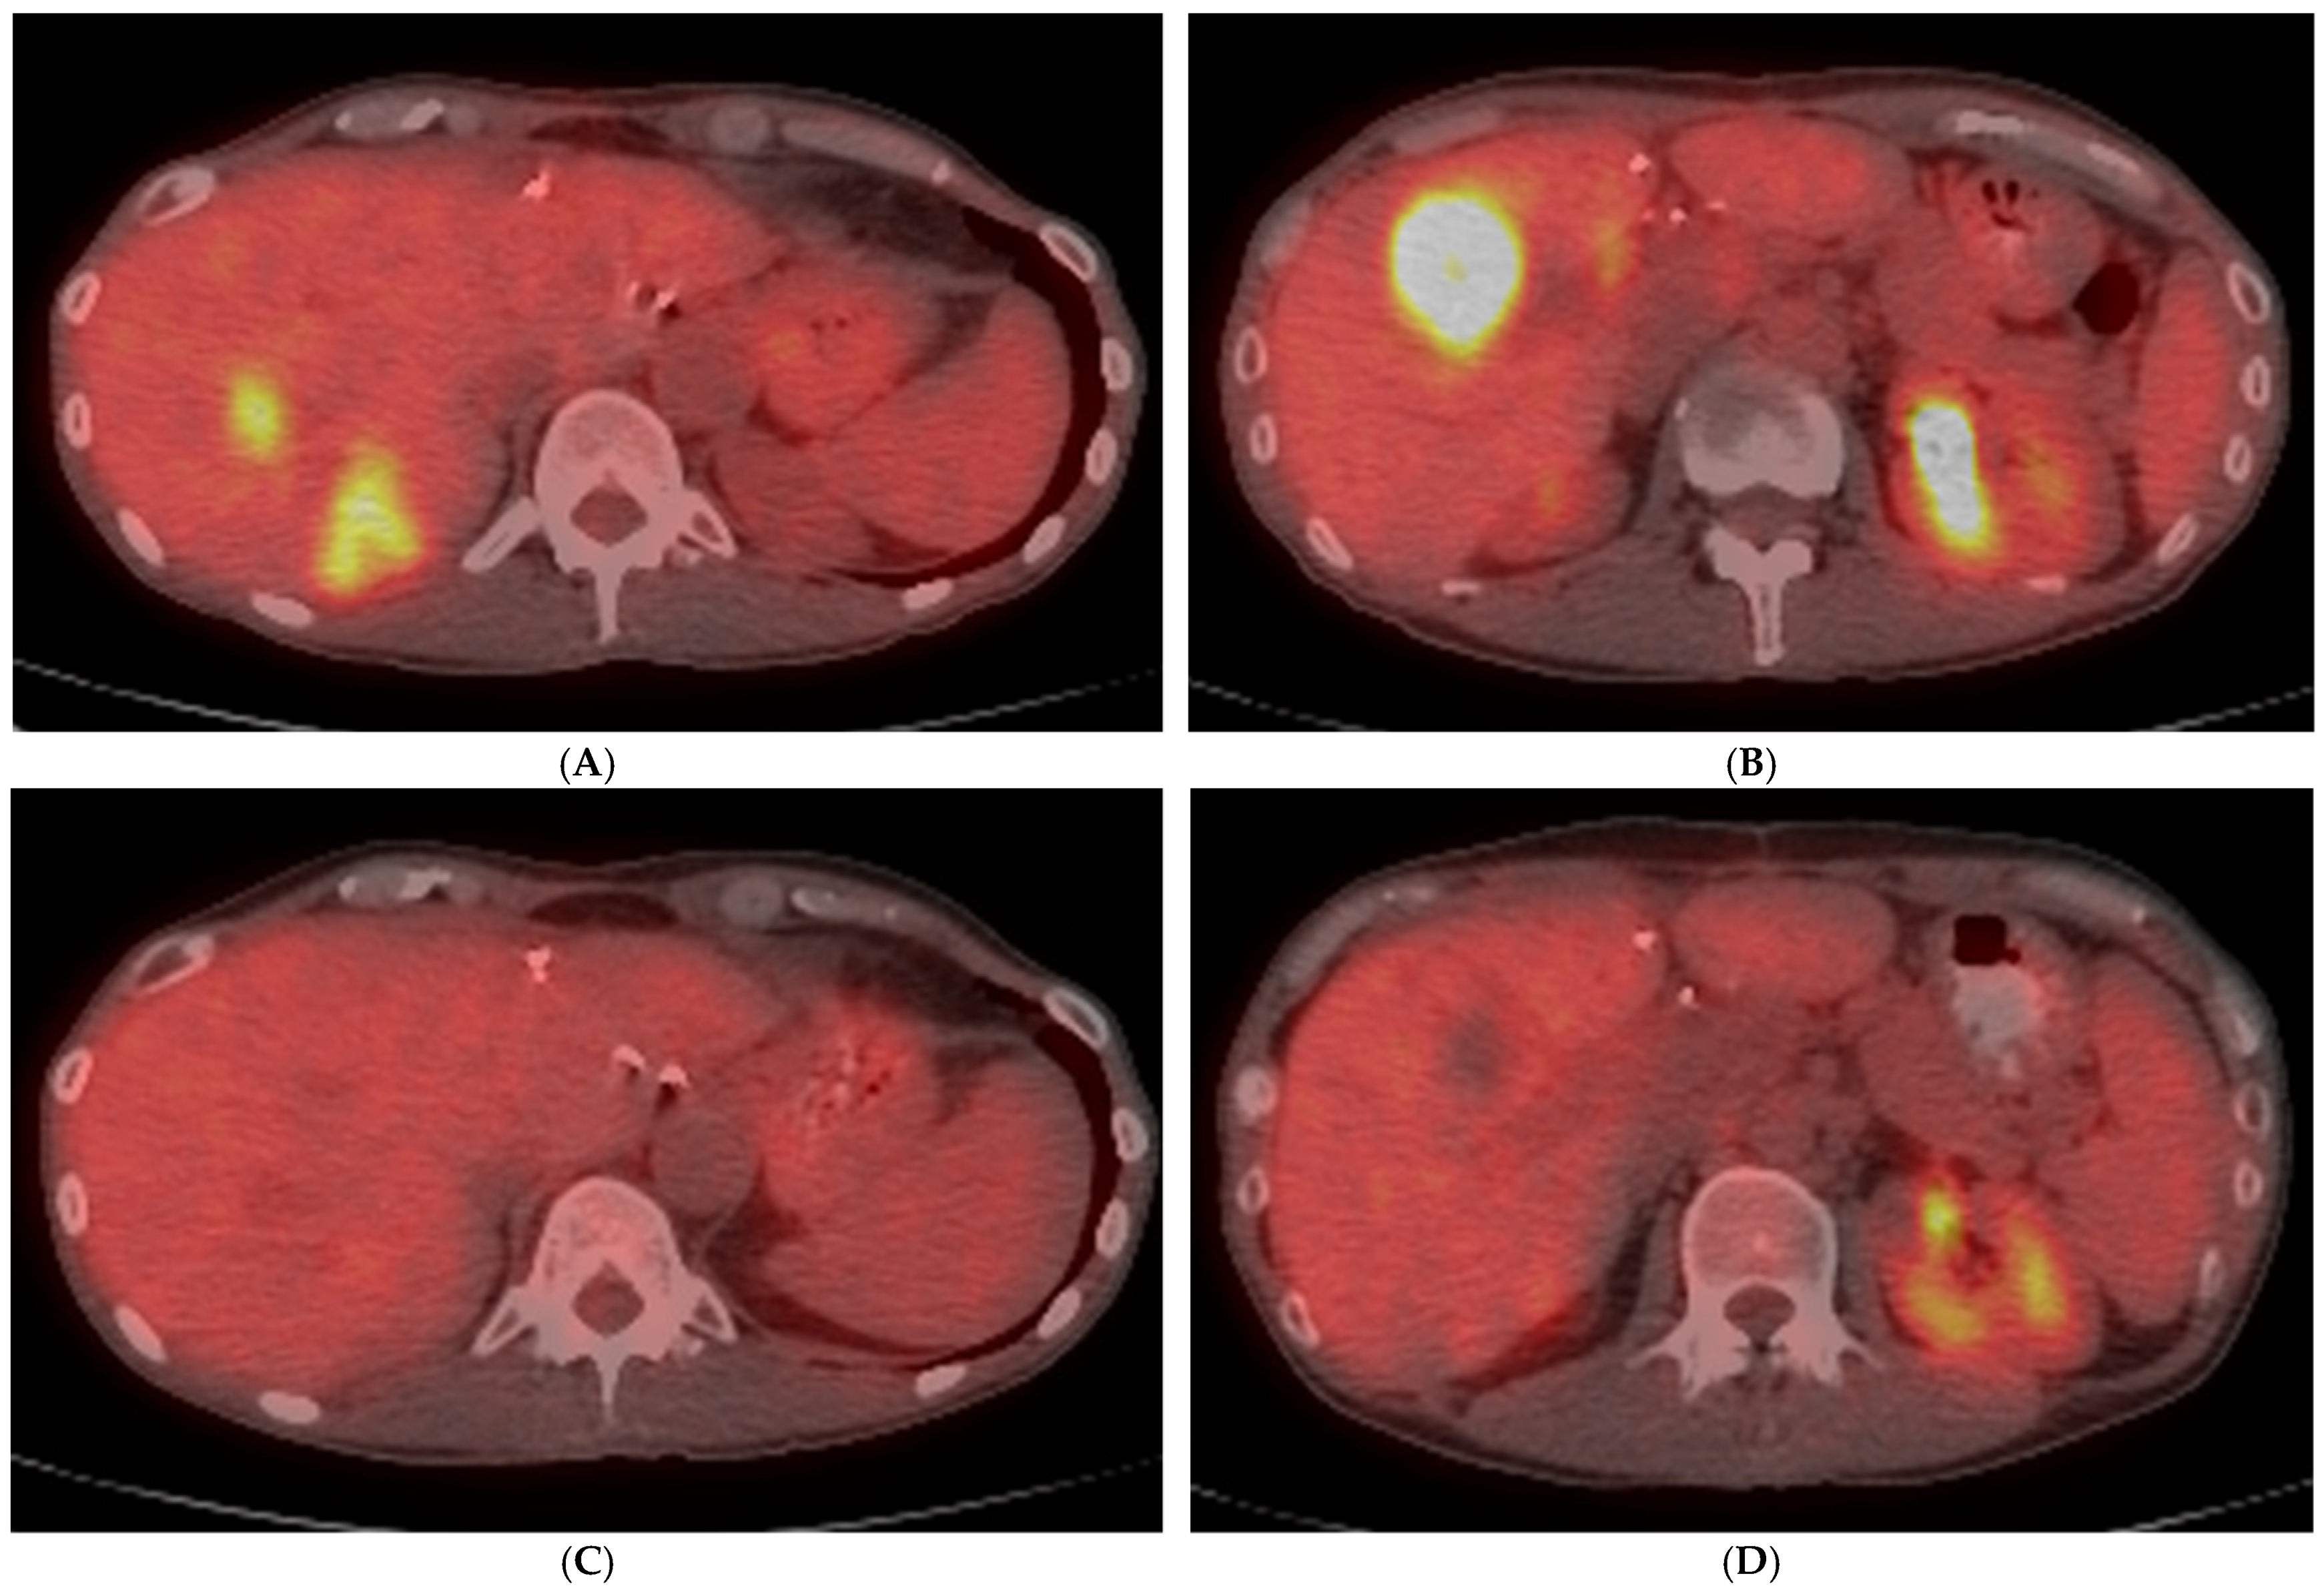

- Zirakchian Zadeh, M.; Yeh, R.; Kunin, H.S.; Kirov, A.S.; Petre, E.N.; Gönen, M.; Silk, M.; Cornelis, F.H.; Soares, K.C.; Ziv, E.; et al. Real-Time Split-Dose PET/CT-Guided Ablation Improves Colorectal Liver Metastasis Detection and Ablation Zone Margin Assessments without the Need for Repeated Contrast Injection. Cancers 2022, 14, 6253. [Google Scholar] [CrossRef]

- Cornelis, F.H.; Petre, E.N.; Vakiani, E.; Klimstra, D.; Durack, J.C.; Gonen, M.; Osborne, J.; Solomon, S.B.; Sofocleous, C.T. Immediate Postablation 18F-FDG Injection and Corresponding SUV Are Surrogate Biomarkers of Local Tumor Progression after Thermal Ablation of Colorectal Carcinoma Liver Metastases. J. Nucl. Med. 2018, 59, 1360–1365. [Google Scholar] [CrossRef]

- Cornelis, F.; Storchios, V.; Violari, E.; Sofocleous, C.T.; Schoder, H.; Durack, J.C.; Siegelbaum, R.H.; Maybody, M.; Humm, J.; Solomon, S.B. 18F-FDG PET/CT Is an Immediate Imaging Biomarker of Treatment Success after Liver Metastasis Ablation. J. Nucl. Med. 2016, 57, 1052–1057. [Google Scholar] [CrossRef] [PubMed]